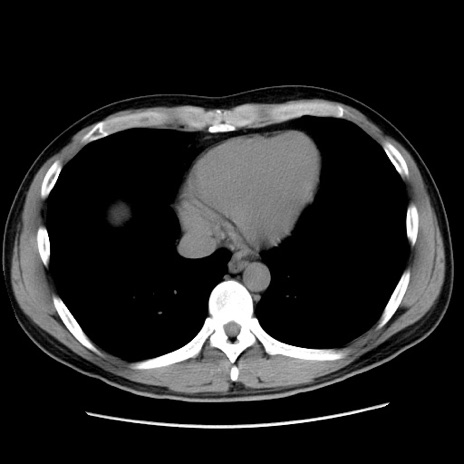

症例36(横断像)

【症例】20歳代 男性

【主訴】心窩部痛

【現病歴】今朝より上腹部痛あり。一旦軽快していたが再度出現したため救急要請。昨日夕に白身の魚を含む刺身を食べた。

【身体所見】BP 136/89mmHg、HR 74/min、BT 37.0℃、腹部:膨満、軟、心窩部に圧痛あり。反跳痛なし、筋性防御なし、腸雑音やや亢進あり。

【データ】WBC 17700、CRP 0.48

冠状断像